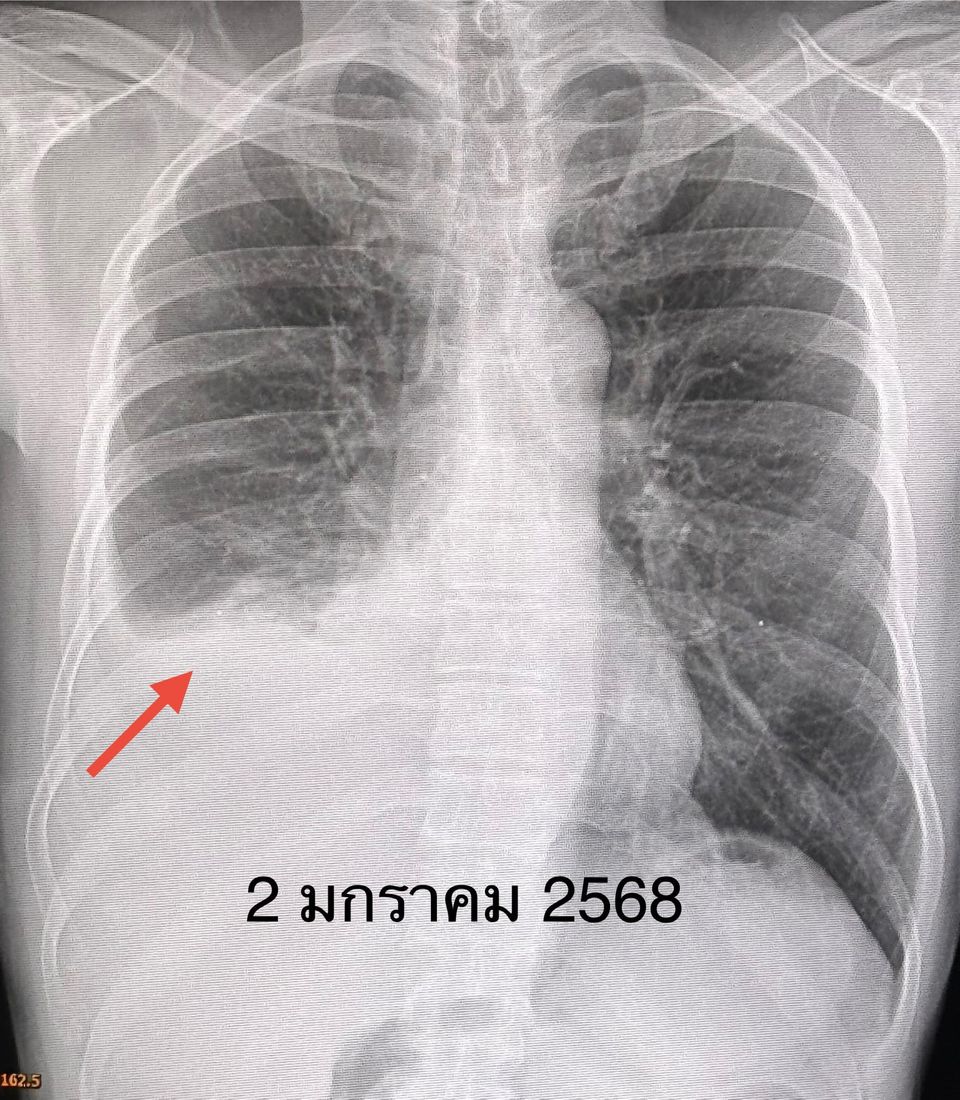

หมอมนูญ ระบุด้วยว่า ผู้ป่วยเคสนี้ มะเร็งกระจายเข้าเยื่อหุ้มปอดข้างขวา ทำให้เกิดน้ำในช่องเยื่อหุ้มปอดข้างขวา ต้องเจาะระบายน้ำ แต่น้ำก็กลับมาอีก ให้เข้านอนโรงพยาบาลเพื่อผ่าตัดเอาชิ้นเนื้อจากเยื่อหุ้มปอด และพ่นแป้ง talc ซึ่งประกอบด้วย magnesium silicate เข้าไปในโพรงเยื่อหุ้มปอด (talc pleurodesis) ใส่ท่อระบายน้ำจากช่องเยื่อหุ้มปอดด้านขวา หลังพ่นแป้ง ไม่พบผลข้างเคียงจากการพ่นแป้ง

หลังเอาท่อระบายน้ำในปอดออกยังมีก้อนเลือดเกาะอยู่ในเยื่อหุ้มปอด แพทย์ส่งชิ้นเนื้อมะเร็งจากเยื่อหุ้มปอด ตรวจพบการกลายพันธุ์ของยีน T790M ที่ตำแหน่ง exon 20 แสดงว่า มะเร็งน่าจะตอบสนองต่อยา osimertinib จึงเริ่มให้ยา Tagrisso (osimertinib) 80 มก.กินวันละ 1 ครั้ง วันที่ 31 มกราคม 2568